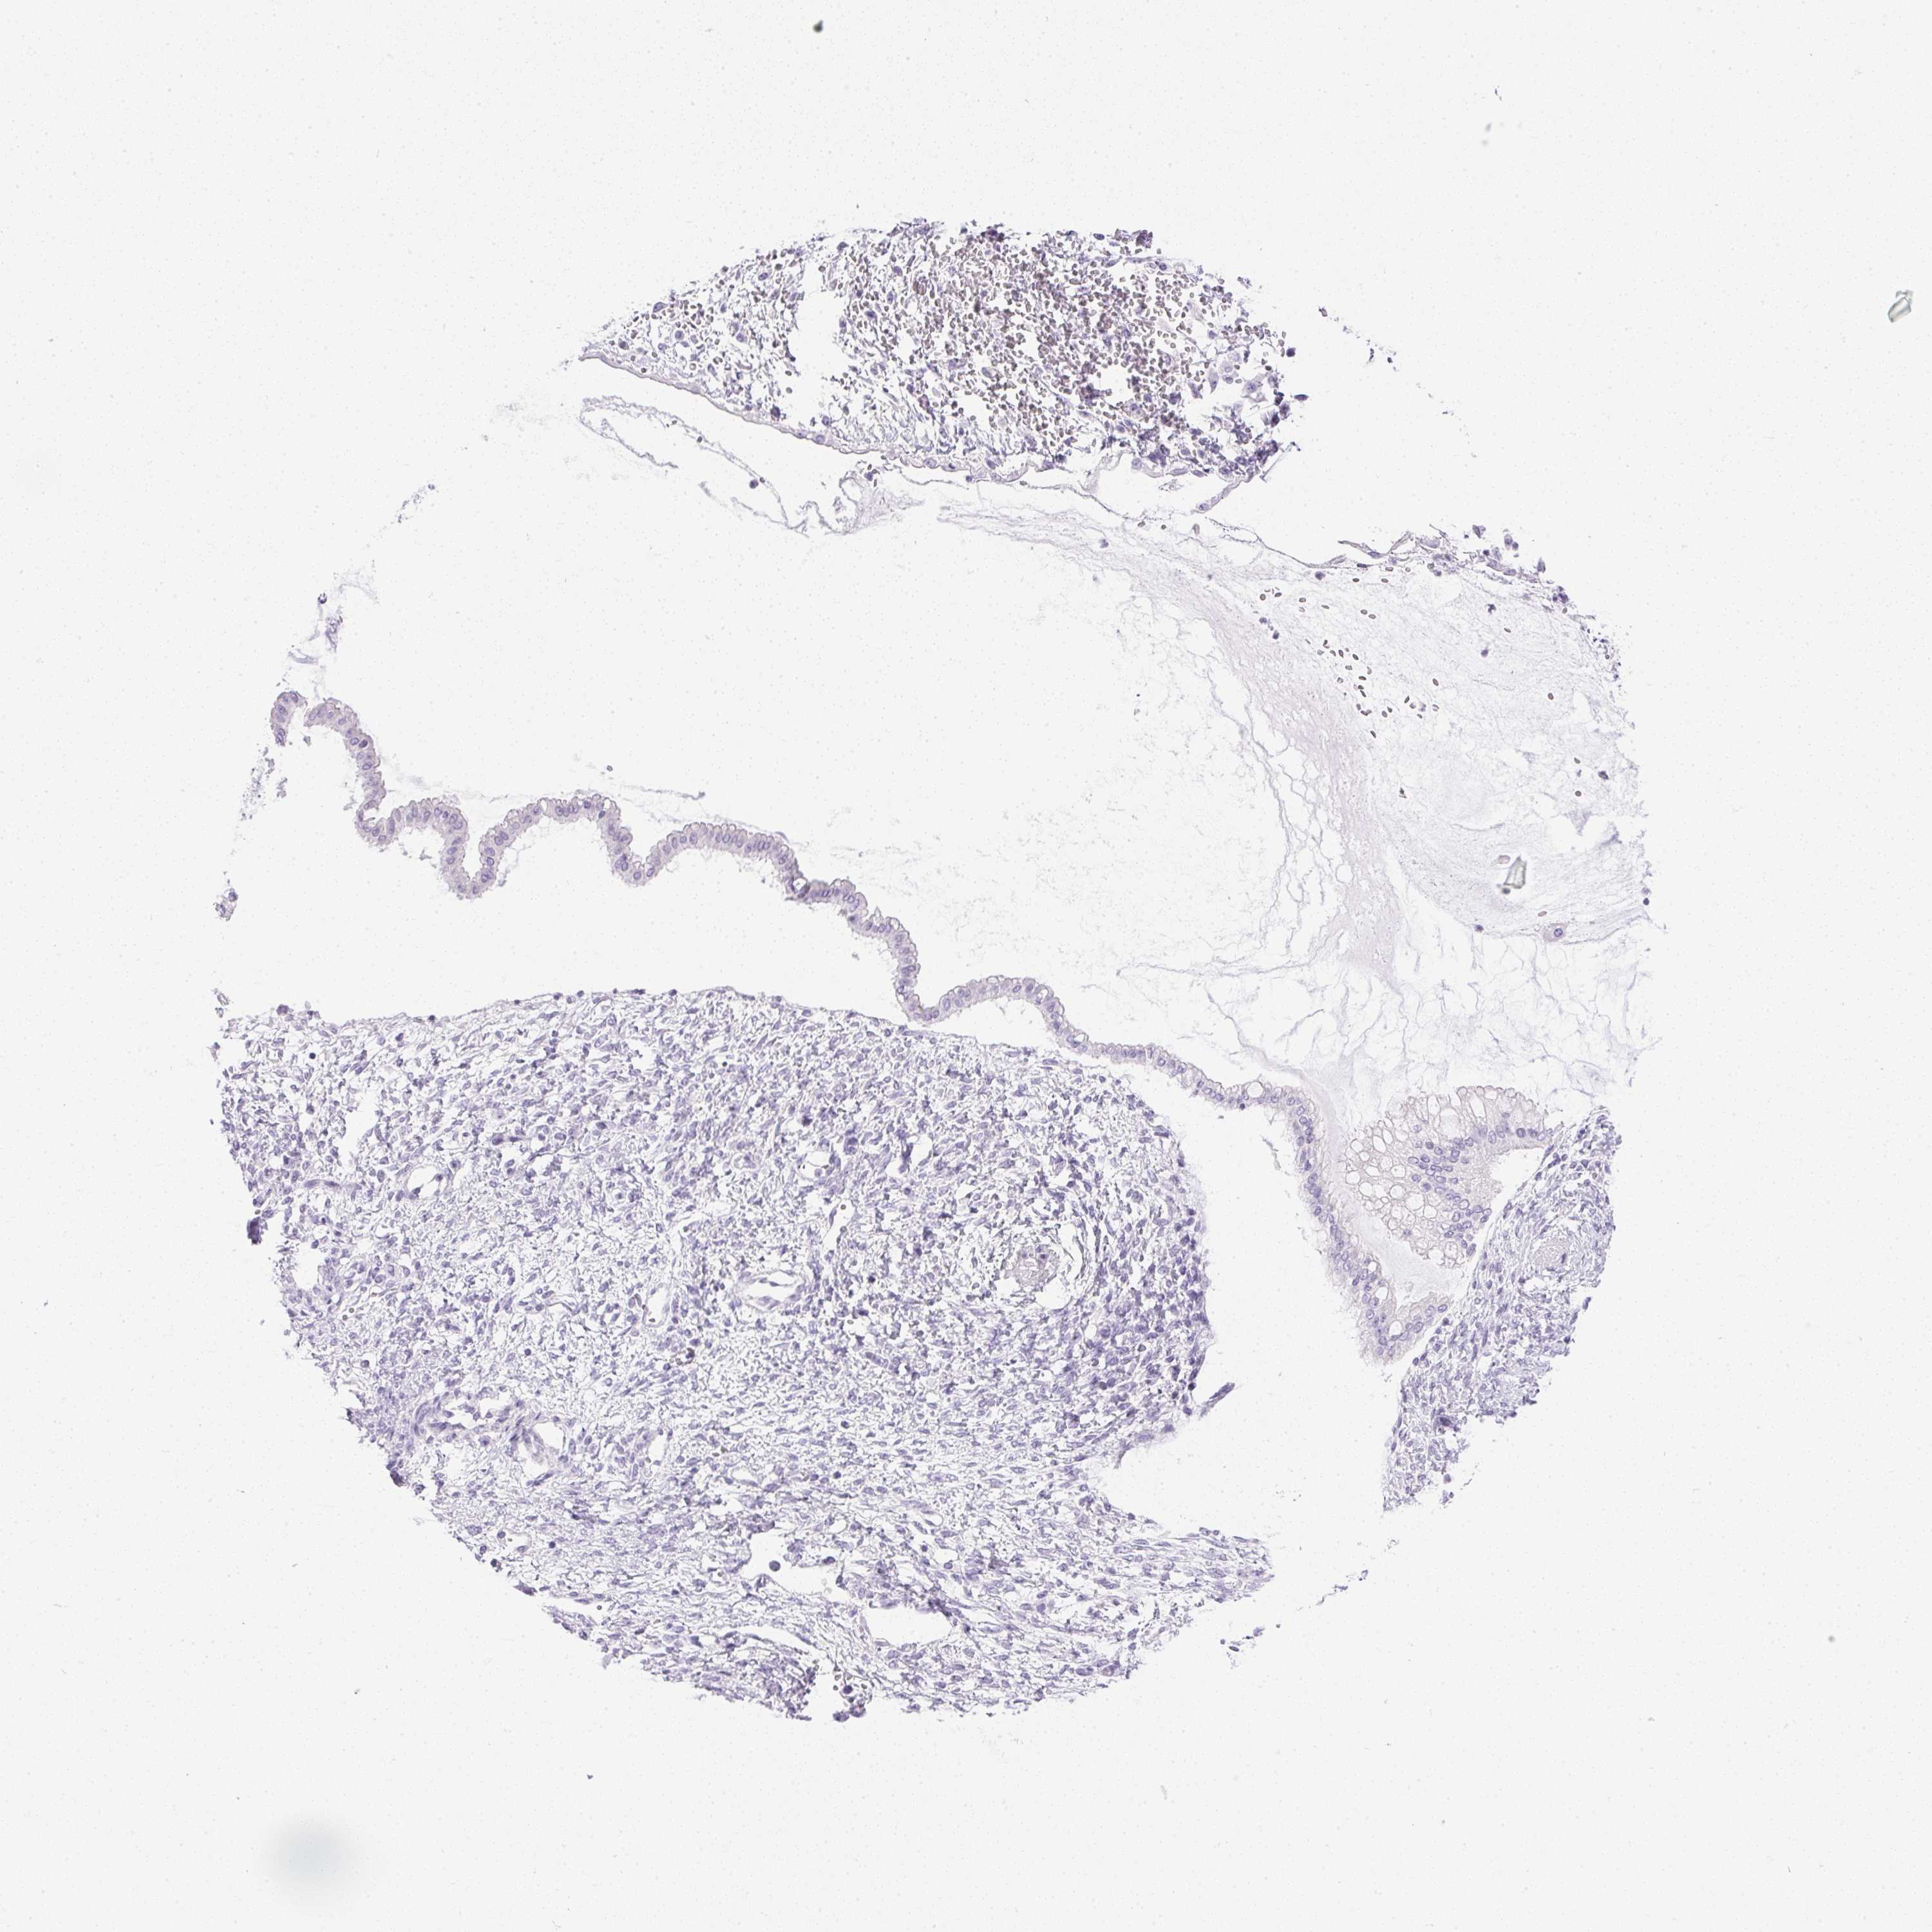

OVARIAN CANCER - Protein expressioni

A mouse-over function shows sample information and annotation data. Click on an image to view it in a full screen mode. Samples can be filtered based on level of antibody staining by selecting one or several of the following categories: high, medium, low and not detected. The assay and annotation is described here.

Note that samples used for immunohistochemistry by the Human Protein Atlas do not correspond to samples in the TCGA dataset.

Antibody stainingi

Antibody staining in the annotated cell types in the current human tissue is reported as not detected, low, medium, or high, based on conventional immunohistochemistry profiling in selected tissues. This score is based on the combination of the staining intensity and fraction of stained cells.

Each image is clickable and will lead to virtual microscopy that enables deeper exploration of all samples and also displays staining intensity scores, fraction scores and subcellular localization as well as patient and tissue information for each sample.

Antibody HPA038069

Antibody HPA046340

Antibody CAB026158

Cystadenocarcinoma, serous, NOS

Carcinoma, endometroid

Cystadenocarcinoma, mucinous, NOS

Carcinoma, NOS